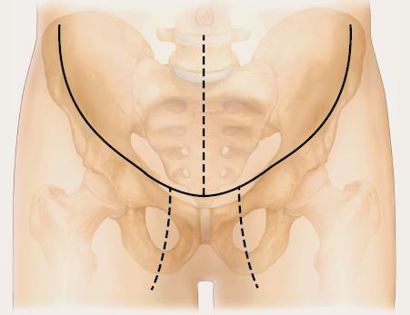

An incision is made that curves across the top of the femur bone.

Developing surgical planes (margins that are tumor free) and separating muscles that can be preserved and leaving those in continuity with the tumor that should be removed, such as the gluteus muscles and iliac. This is based on preoperative MRI and intraoperative findings as well as the type of tumor.